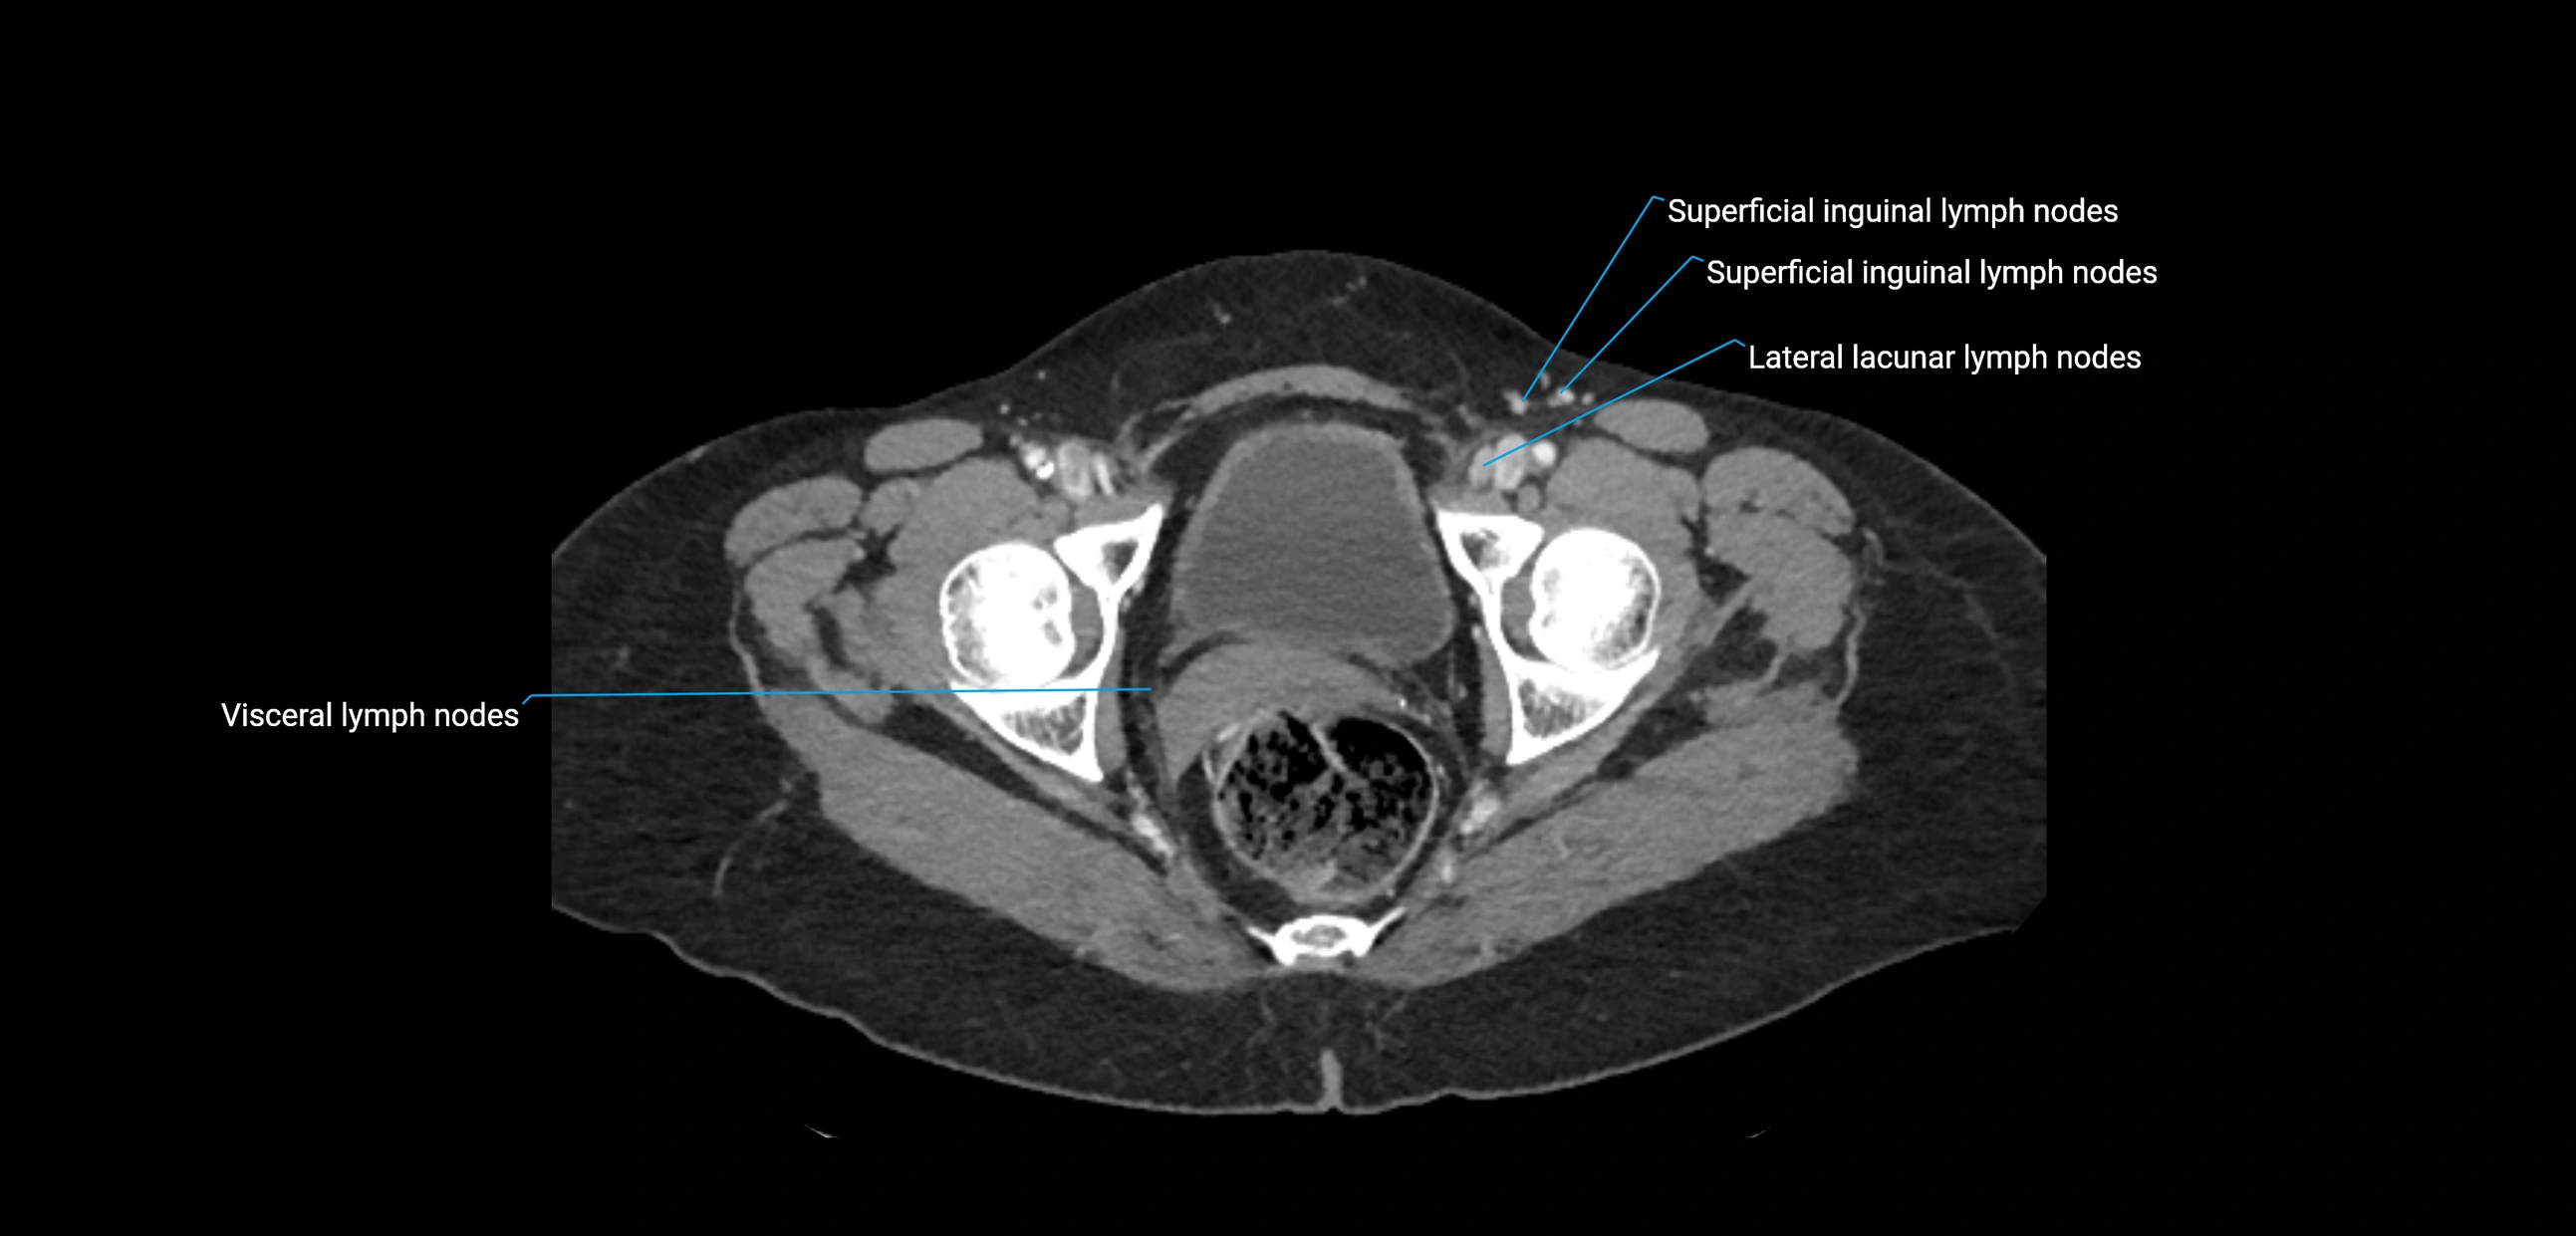

CT image

image